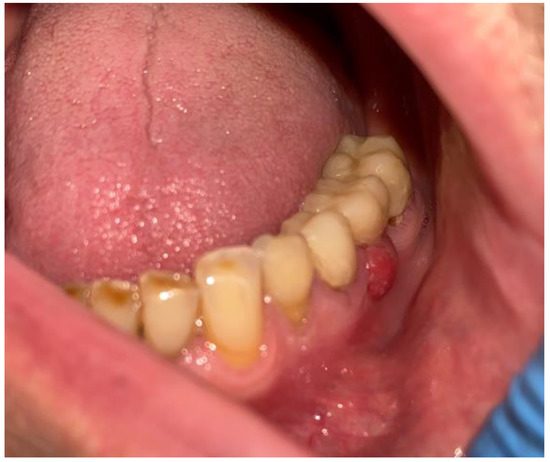

2. Case Description